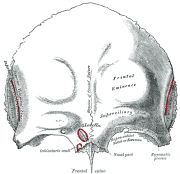

| 2021年7月26日 (一) 18:31 | Gray134.png (文件) |  |

38 KB | 77921020 | Uploaded with SimpleBatchUpload | 1 |